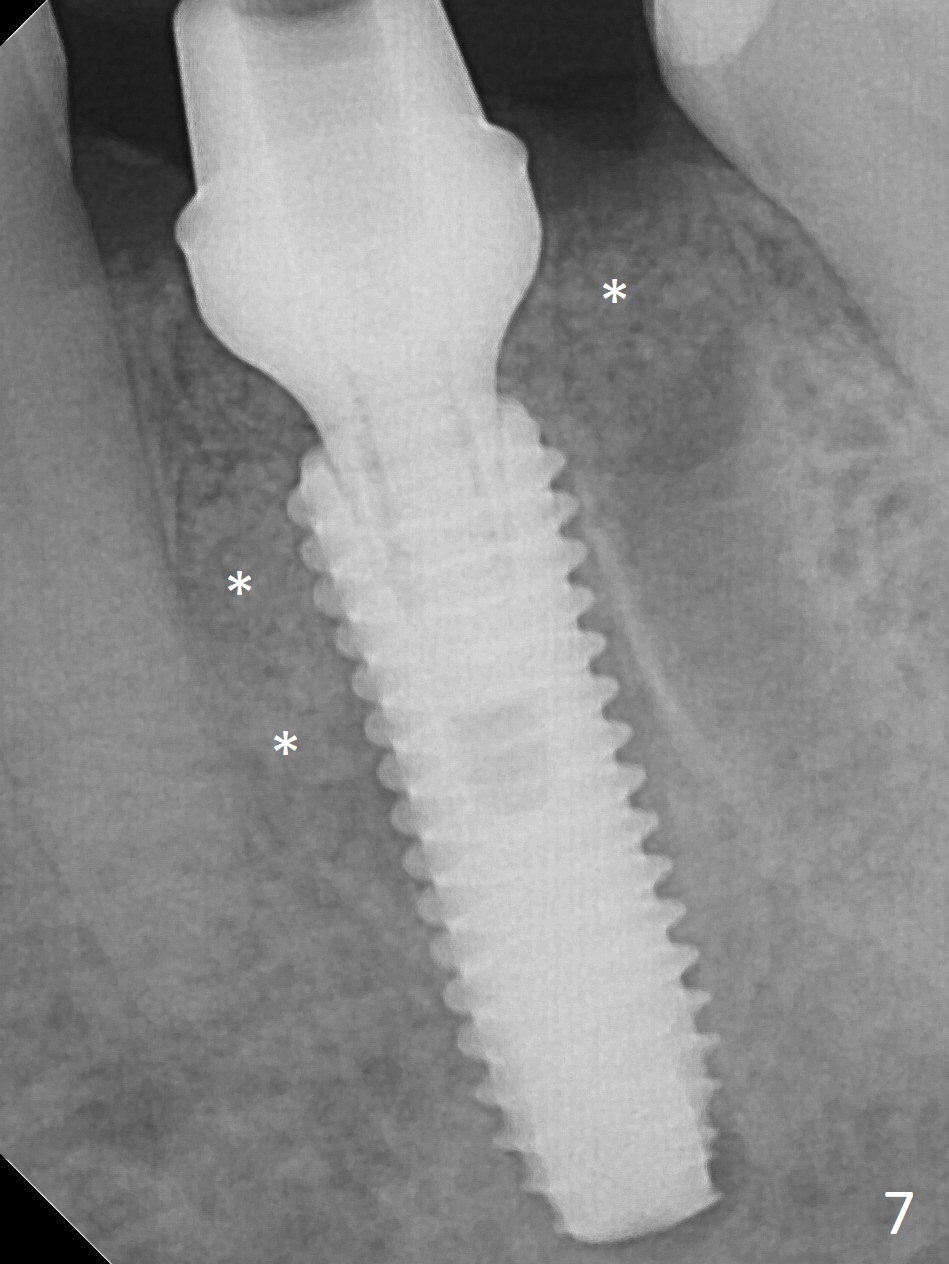

When the patient returns 9 months later, there is severe buccal gingival recession and abscess at #19 (Fig.1 *) with large mesial periradicular radiolucency (Fig.2 *).  The septum is thin and the buccal crest is low after extraction (Fig.3 * (mesial root vertical fracture)).  Osteotomy is initiated in the mesial socket immediately against the septum (Fig.4.5) with ~ 5 mm in the native bone.  Due to severe buccal plate resorption, a shorter implant is placed (Fig.6; 5x15 mm in stead of 18 mm).  There is at least 2 mm gap buccally for Vanilla Graft, which is also placed next to the implant and the neighboring root (Fig.7 *).  There is clearance from the Inferior Alveolar Canal (Fig.8 red dashed line).  Both the mesial and distal sockets heal 5.5 months postop (Fig.9), although the apical portion of the distal socket was not filled with allograft (Fig.7).  The implant was placed mesial.  The straight abutment (6.5x4(4) mm) (Fig.10) is changed to an angled one (5.5 x15 degrees 3 mm cuff (Fig.11)) before impression.  The implant is also placed buccally.  Therefore the implant position is far more important than its length.  The abutment is retightened 2.5 months post cementation, which is related to mesiobuccal placement of the implant (Fig.12).  An ideal trajectory is determined by drawing 2 horizontal lines (at crestal and apical levels: red lines in Fig.13), finding a central point of each line (vertical short line) and joining these 2 central points (Fig.14 pink line).  In fact the ideal osteotomy should have been established distal to the septum in this case.  Guided surgery may alleviate the issue.  The crown is not loose, but the patient feels that the implant tooth cannot sustain mastication.  In fact the screw is removed with hand driver (not wrench).  The abutment hex is rounded and worn.  A new 5.5x4(4) mm abutment is placed (without knowledge of previous use of an angled abutment) with mesial reduction to reduce undercut and buccodistal margin lowered to reduce gingival embrasure. It is that the straight abutment could decrease the chance of screw loosening.  Otherwise the implant has to be removed for better trajectory.